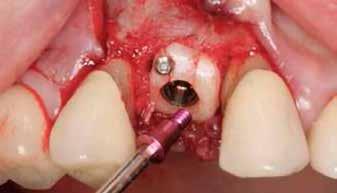

A fogak eltávolítása minimálinvazív módon történt, amelynek során a parodontális rostokat egy periotom segítségével átvágtuk, így lebenyes feltárásra nem volt szükség (3. a–b ábrák) . Az implantátumokat a frissen eltávolított fogak alveolusaiba ültettük be. A foghúzást követően minden alveolust alaposan ellenőriztünk az endodontiai, vagy parodontális eredetű gyulladásos szövetmaradványok eltávolítása érdekében, majd fiziológiás sóoldattal bőségesen átöblítettük. Megfelelő előfúrást követően a kerámiaimplantátumokat 30 fordulat/perc sebességgel és 35 Ncm behajtási nyomatékkal helyeztük be (4. a–b ábrák) . A réseket csontpótlóval töltöttük ki (Maxresorb ® 0,5–1,0 mm szemcseméret, 0,5 cm 3 térfogat, Straumann ®; 6. ábra ).

3. ábra: Intraorális kiindulási állapot. – 4. ábra: A terület intraorális nézetből. 5. ábra: A lebenyes feltárást követően laterális és vertikális csonthiány látszik a 1.4 területén. – 6. ábra: Az Easy Bone Collector egy egyedi műszer, amely trepánfúrót, belső hűtést, kerámia csapágyakat és integrált lágyrészvédelmet tartalmaz. Mindez megkönnyíti a csontlemezek eltávolítását. – 7. ábra: A semilunaris technika és az Easy Bone Collector együttes alkalmazása több kortikális csontlemez kinyerését teszi lehetővé a retromoláris régióból.